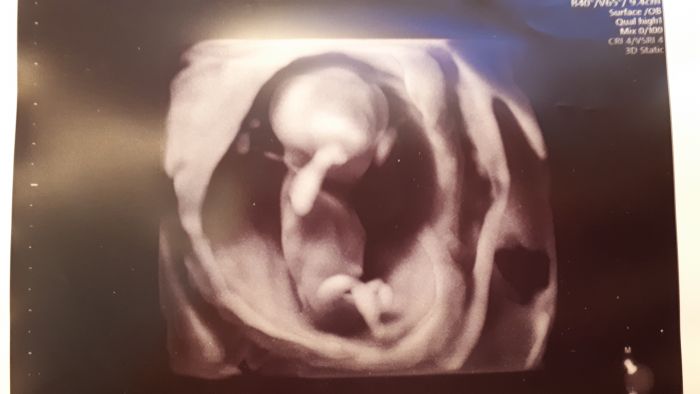

Ahojky, hlásím, že včerejší screening dopadl na jedničku:)) Dokonce paní doktorka už hematom nikde nenašla, takže snad už je to vše za námi a můžeme se pořádně začít těšit na další miminko:) Už nám chtěla hlásit pohlaví, ale odolali jsme, bude překvapeni:). Jediné co, tak mám vyšší riziko preeklampsie, ale myslím si, že se mě to nakonec týkat nebude, jediné, co k tomu MUDr. vedlo byl větší odpor cév na levé straně, tlak mám klasicky nízký, tak snad bude tohle bezpředmětné, budu ale brát pro jistotu celé těhotenství nějaké léky. Posílám fotku toho našeho broučka, dcera říká, že brášky:D A přeji vám všem krásné Vánoce, ať jsou jen samé pozitivní reakce pro ty, co si oznámení těhotenství nechávají pod stromeček:)